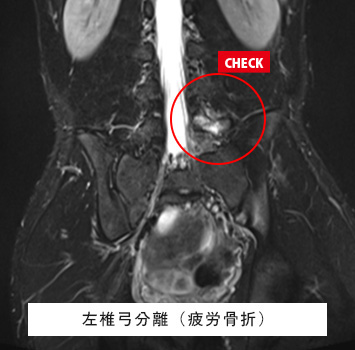

腰椎MRIチェック

このような方におすすめします。

• 慢性的に腰が痛い、重い

• おしり〜太もも、足に痛みやしびれがある

• ヘルニアや加齢による変化(変形性腰椎症)、ぎっくり腰が心配

• 尻もちをついた、スポーツや仕事で腰に負担がかかった後の腰痛

筋肉と関節痛みのMRIチェック名古屋なら

レントゲン検査では分からない椎間板、筋肉、靱帯などの様子が

がたった10分の検査で評価出来ます!

腰下肢痛、レントゲンで異常なし

スポーツを続けており強い腰痛、レントゲンで異常なし